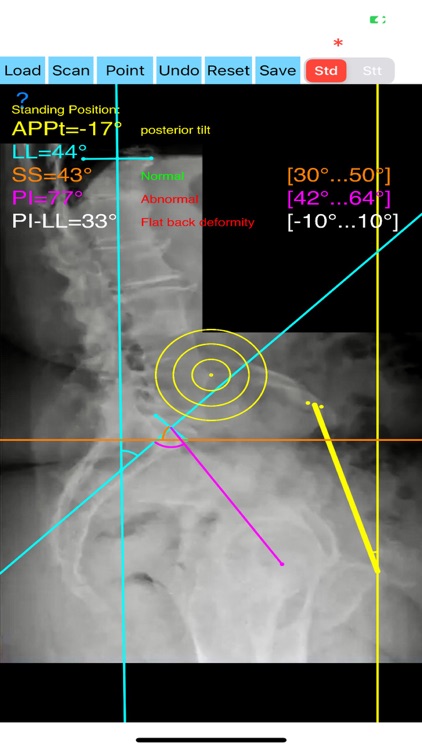

Evaluation of functional spinopelvic imaging in lateral radiographs in sitting and standing positions is of importance, especially in patient before total hip replacement surgery. Patients with concomitant hip and spine pathology undergoing primary total hip were identified as being at high risk for dislocation. Instability-prone patients arhtroplasty (THA) should appropriately assessed for the presence of deformity and abnormal spinopelvic mobility. The preoperative planning for THA should encompass evaluation of functional spinopelvic imaging in lateral radiographs in sitting and standing positions. Before planning cup position the surgeon should taken into account also anterior pelvic plane (APP) the coronal (functional) plane and the anterior pelvic plane tilt APPt or pelvic tilt and abnormal spinopelvic mechanics from standing to sitting.

The App is software aimed for orthopaedic surgeons, and allow to:

-securely import medical images directly from the camera or stored photos.

- mark certain points at the image of X-ray, and calculate at once the anterior pelvic plane tilt (APPt) or pelvic tilt , Pelvic incidence (PI), Sacral slope (SS), Lumbar lordosis (LL), Pelvic incidence Angle (PI) minus Lumbar lordosis Angle (LL)(PI–LL).

-to classify the patient into one of four Categories of the Hip-Spine Classification (1A,1B,2A,2B) by integrating spinal alignment (spinal deformity defined at PI-LL mismatch >10 degree(1)

-cases are categorised to group-specific recommendations for acetabular cup position respectively thus with minimal measurements will effectively identify the complex “hip-spine” THA patient at high risk for postoperative instability (1).

-According to measured parameters in standing and sitting lateral x- rays - based n a busy everyday practice, app offers a convenient way to perform radiographic measurements for spine, at the spinopelvic juncture - combing sitting and standing X-Rays, in a blink of an eye in front of your screen. The build in features of the app, allows results to be categorized and may help identify the complex “hip-spine” THA patient at high risk for postoperative instability and helps planning the optimum cup placement.